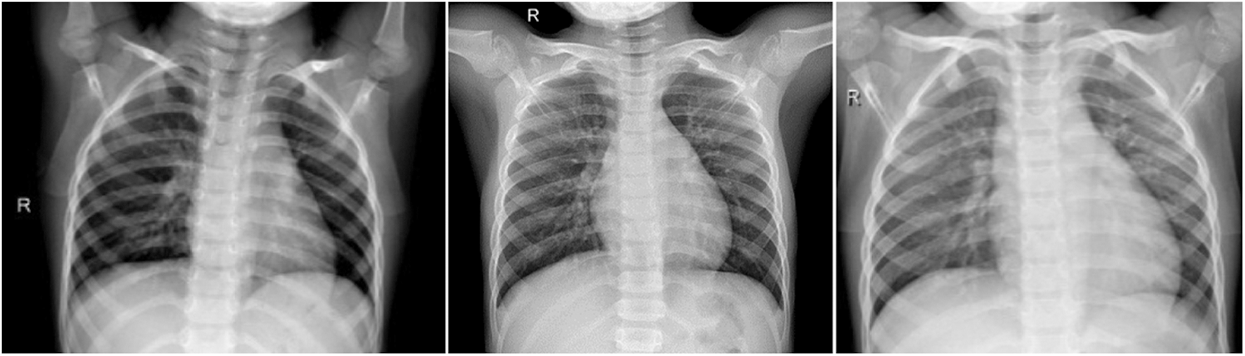

This the healthy period or group, which mean the X-ray image the patient has no COVID-19 infection. In this group, we have total of 1845 X-ray images. Fig. 2 shows samples of chest X-ray images of Group A.

Figure 2: Chest X-ray images of Group A (no infection)